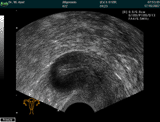

Ultraschall des Eierstocks

Bei der gynäkologischen Ultraschalluntersuchung, die entweder von der Scheide oder von der Bauchdecke aus durchgeführt

wird, erfolgt eine Darstellung und Beurteilung der inneren Genitalorgane. In der Hand des erfahrenen Untersuchers

können hierbei bereits sehr kleine Veränderungen frühzeitig festgestellt werden.